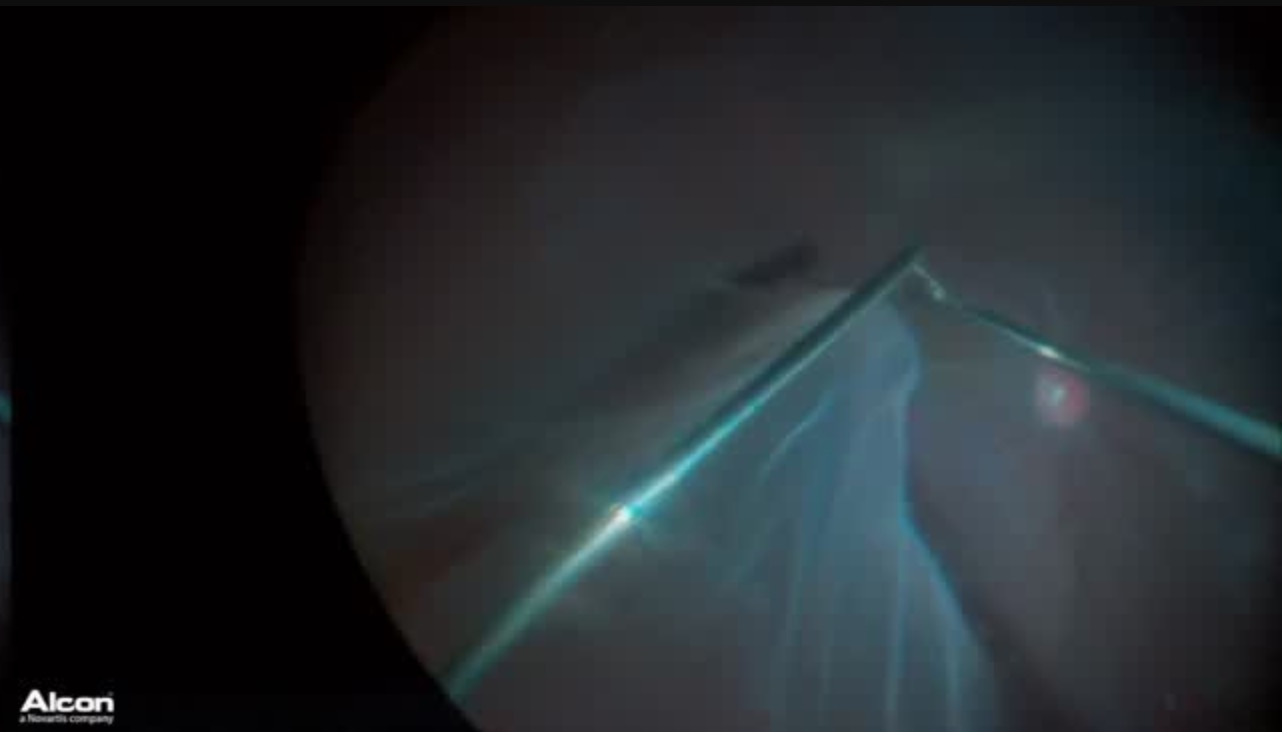

Intraoperative Fluorescein Angiography

Alan J. Franklin, MD, PhD